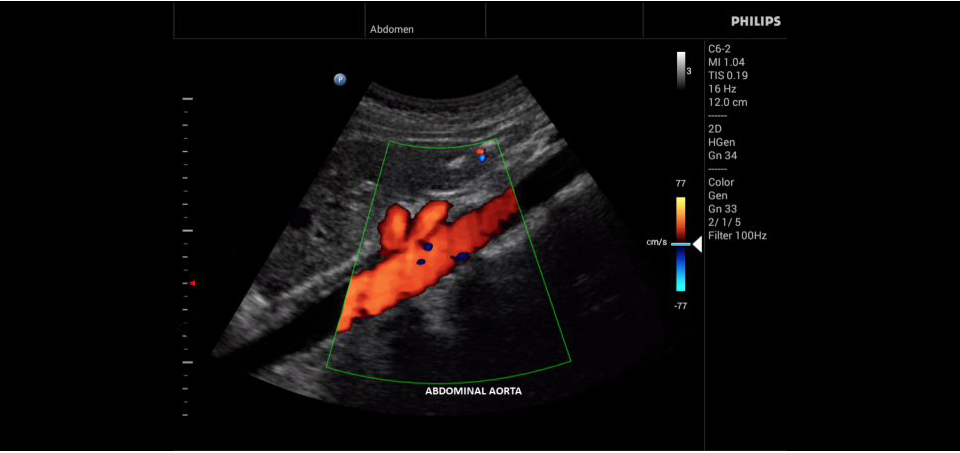

• Конвексный УЗИ датчик Philips С6-2

• Цветное допплеровское картирование

• Исследования сосудов;

• Непрерывный волновой допплеровский режим: Этот режим полезен в случаях, когда кровоток имеет высокую скорость, например, при аортальном стенозе, и может использоваться для повышения надежности диагностики.